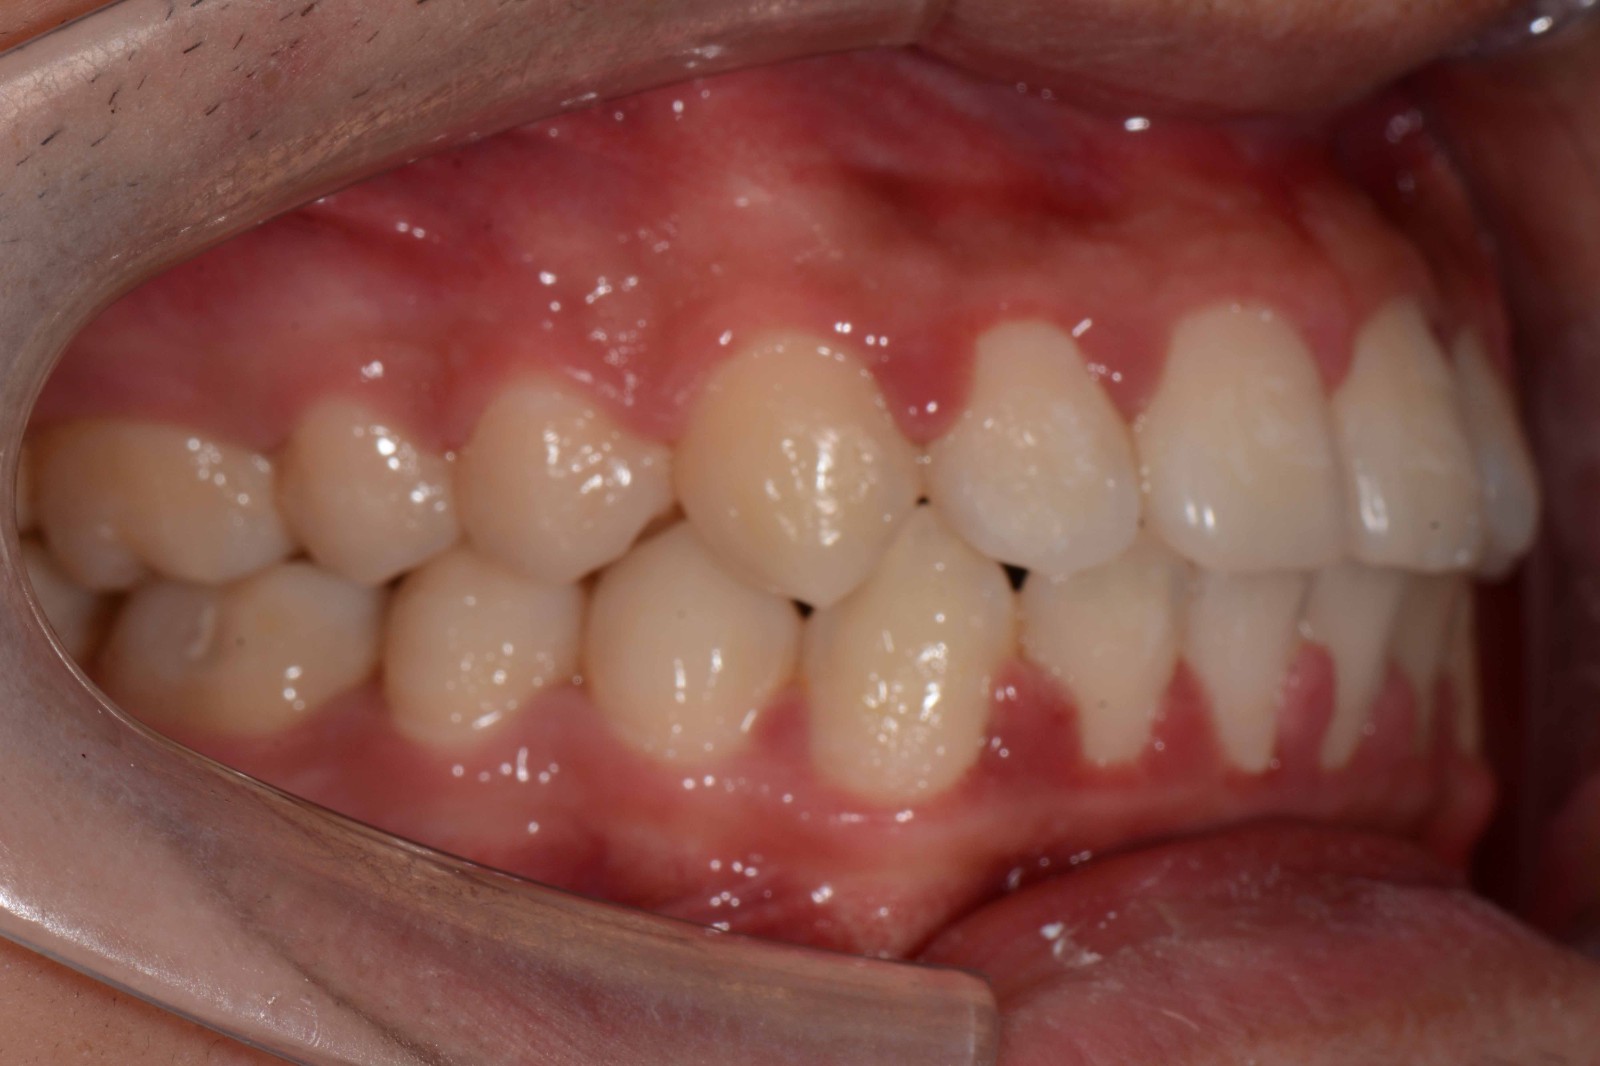

检查:拍摄口内面像照片,拍摄全景片侧位片,口扫,上下颌I-II度拥挤,中线不齐,局部反合,磨牙基本中性关系,上下前牙比较直立。

诊断:安氏I类错颌畸形

矫治前: